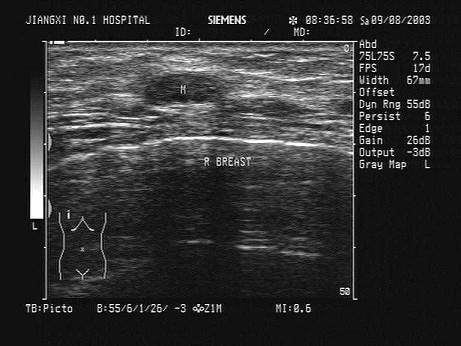

问题 某患者自诉乳腺可触及一包块,光滑可移动,超声图像如图,诊断为?(?)

选项 A.纤维瘤 B.囊肿 C.乳腺癌 D.小叶增生 E.乳腺导管扩张

答案 A